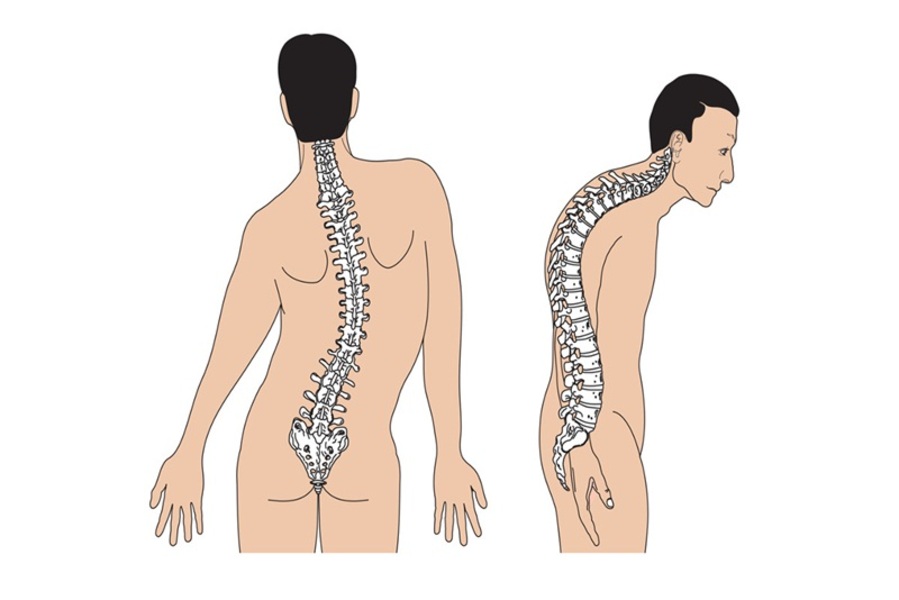

xem chi tiếtCong vẹo cột sống

Cong vẹo cột sống là một tình trạng biến dạng ba chiều của cột sống, không chỉ đơn thuần là “tư thế xấu”. Thay vì thẳng, cột sống bị cong sang một bên theo hình chữ “C” hoặc chữ “S”, và đồng thời các đốt sống cũng bị xoay.